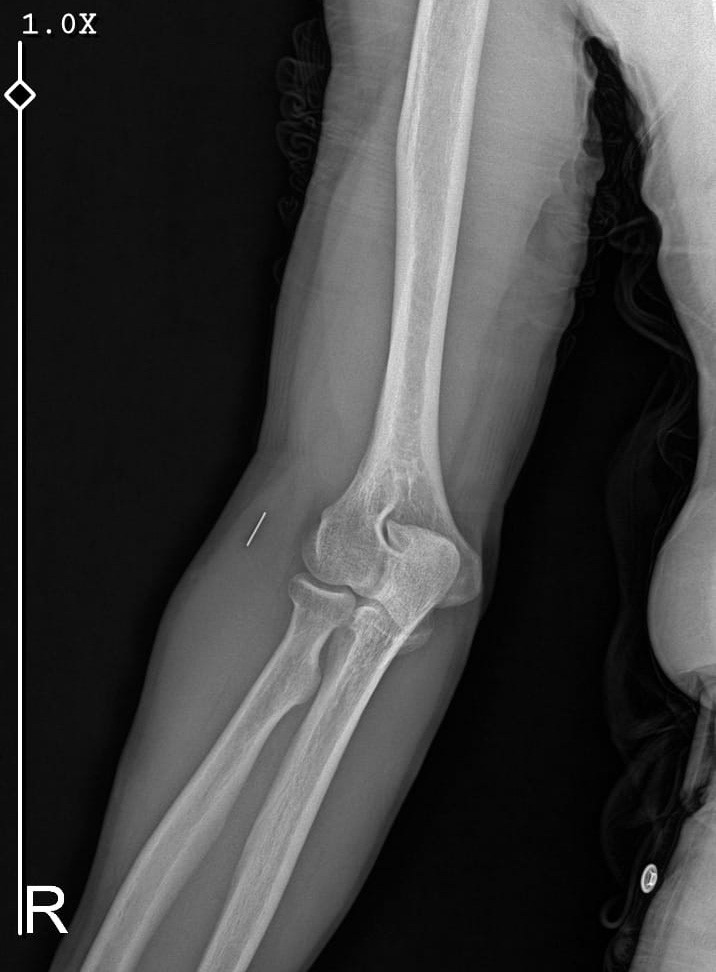

Öte yandan, ameliyatların ardından ağrıları devam eden Güleryüz’ün kolunda metal parça bulunduğu ve bu parçanın parmak bölgesinden dirseğe doğru ilerlediği öne sürüldü. Ayrıca, fabrikada temizlik personeli olarak çalışan Nurettin Güleryüz’ün hastane sürecinde işten çıkarıldığı da öğrenildi.

“Doktorlara bileğime doğru ağrılarım olduğunu sürekli ifade etmeme rağmen beni dinlemediler. Sonradan kolumda metal kaldığını öğrendik. Bunun ihmal olduğunu düşünüyoruz. Çünkü kola metal nasıl girebilir? Ben 9 aydır çalışamıyorum. Kalp rahatsızlığım sebebiyle yüzde 46 engelliyken şu anda yüzde 75 engelli durumuna düştüm. Erken emeklilik dilekçesi verdim ancak henüz sonuç gelmedi. Bu konuda çok mağdurum. Yetkililerin bunu duymasını istiyorum. Savcılığa suç duyurusunda bulunduk. Yaklaşık 9 aydır henüz soruşturma izni gelmedi. Süreci bekliyoruz, henüz dava açılmış değil. Kolumda bırakılan metal ilerliyor. Pazartesi günü bunun için de operasyon geçireceğim. Çıkarılıp çıkarılamayacağı net değil. Elimde titremelerim var, çalışamıyorum ve işveren tarafından işten çıkarıldım. Yetkililerden destek ve konunun incelenmesini talep ediyorum. ”